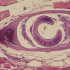

Профилактика трихинеллёза